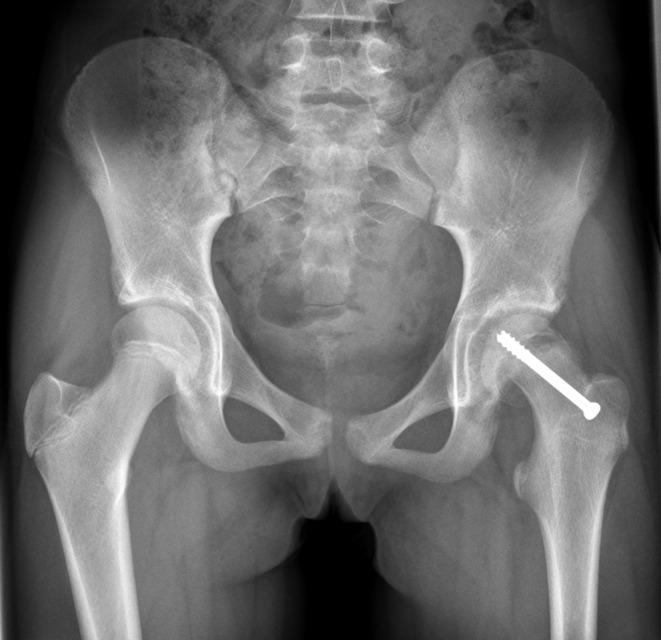

Background: Accurate repositioning of the femoral head in patients with Slipped Capital Femoral Epiphysis (SCFE) undergoing Imhäuser osteotomy is very challenging. The objective of this study is to determine if preoperative 3D planning and a 3D-printed surgical guide improve the accuracy of the placement of the femoral head.

Methods: This retrospective study compared outcome parameters of patients who underwent a classic Imhäuser osteotomy from 2009 to 2013 with those who underwent an Imhäuser osteotomy using 3D preoperative planning and 3D-printed surgical guides from 2014 to 2021. The primary endpoint was improvement in Range of Motion (ROM) of the hip. Secondary outcomes were radiographic improvement (Southwick angle), patient-reported clinical outcomes regarding hip and psychosocial complaints assessed with two questionnaires and duration of surgery.

Results: In the 14 patients of the 3D group radiographic improvement was slightly greater and duration of surgery was slightly shorter than in the 7 patients of the classis Imhäuser group. No difference was found in the ROM, and patient reported clinical outcomes were slightly less favourable.

Conclusions: Surprisingly we didn't find a significant difference between the two groups. Further research on the use of 3D planning an 3D-printed surgical guides is needed.